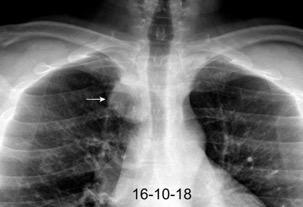

Neumonía a neumococos base izda. con derrame que aumenta.

Broncograma en lateral y en US.